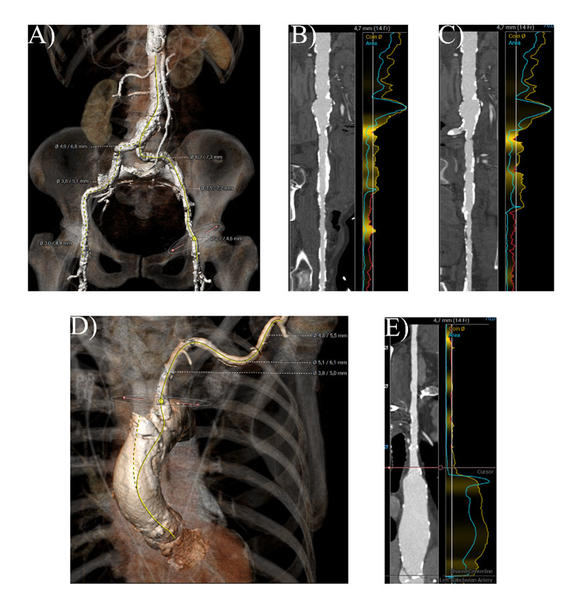

Darüber hinaus stellte sich bei paVK die ungünstige Anatomie der Beckenarterien dar, mit minimalen Lumendurchmessern von 2 mm in der A. iliaca communis, der A. iliaca externa und der A. femoralis communis auf beiden Seiten (Abbildung 3, Video 7, Video 8).

Abbildung 3. CT-Analyse des femoralen und linken axillären Zugangs. A) 3D-Rekonstruktion der Becken- und Femoralarterien B) Snake-Ansicht der rechten Beckenachse C) Snake-Ansicht der linken Beckenachse D) 3D-Rekonstruktion der linken Axillar- und Subclaviaarterie E) Snake-Ansicht des linken axillären Zugangs